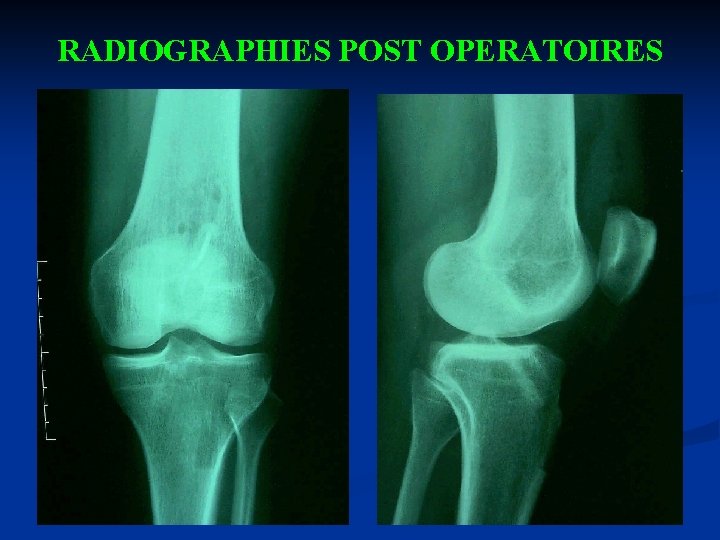

RADIOGRAPHIES POST OPERATOIRES

COMPLICATIONS n n n Complications d’anesthésie. Thrombophlébite. Infections post-opératoires. Problème avec le greffon (la revascularisation dure environ 3 mois. Quand la revascularisation est complète, le greffon se renforce progressivement). Problème du site donneur (gêne pour la position agenouillée, fracture de la rotule, tendinite du tendon rotulien, mauvais récupération du quadriceps, fibrose au niveau du tendon entraînant une raideur).